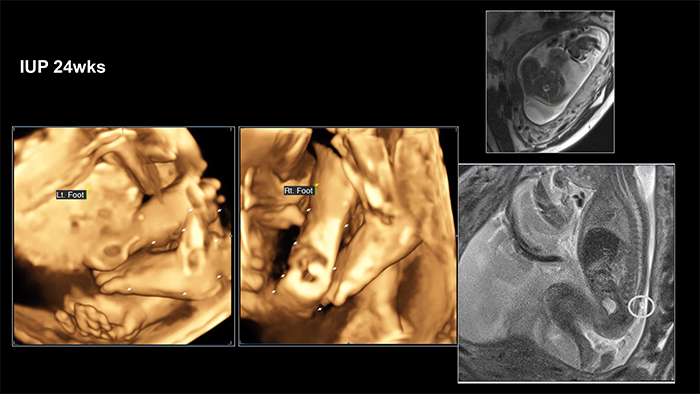

A 36-year-old woman, diagnosed with fetal myelomeningocele (mmc), visited outpatient clinic at 24 weeks and 0 days’ gestation. She said that everyone told me to give up the baby.

Chiari II malformation was suspected on ultrasonography and fetal MRI. However, sac size was small and fetal leg movements were active. A multidisciplinary counselling was performed. Although mmc of the fetus had been progressed slowly after 30 weeks’ gestation and mother received cesarean section at 35 weeks’gestation due to preterm labor, the neonate received immediate postnatal operation for mmc.